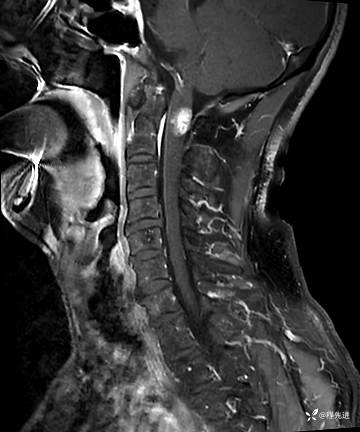

MRI平扫+增强:

T1: